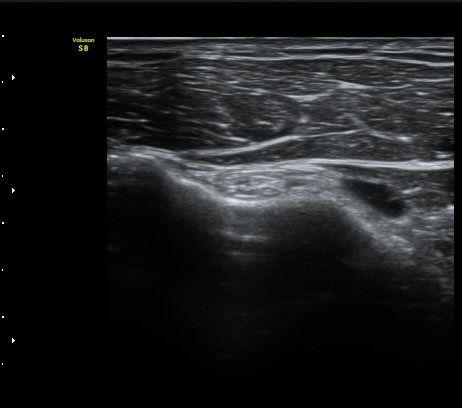

¿À±¸µ¹±â Ⱦ´Ü¸é°Ë»ç»ó ¿Áµ¹±â ¾Æ·¡, ³»Ãø, °ß°©ÇÏ±Ù°Ç Ç¥Ãþ¿¡¼­ ¼ö¾×Àú·ù°¡ °üÂûµÈ´Ù

(±×¸² 3, 4).